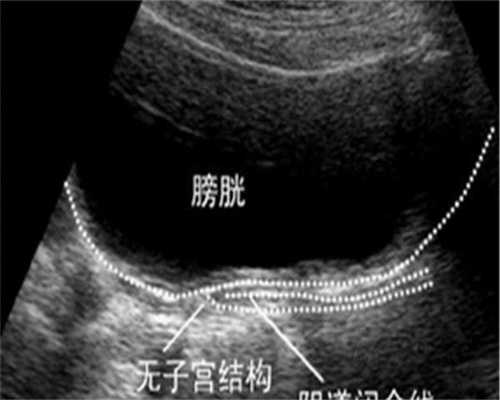

平顶山所在的医院现在做不了试管婴儿,而平顶山所在城市的其他医院也做不了试管婴儿,所以本市的不孕不育患者要做试管,只能去其他城市,比如同省的漯河、郑州、洛阳等、 而省会城市!郑州 能做 试管的 医院 更多,试管一次上床成功的概率也更高,可高达 65% 左右。不过,无论选择在哪里做 试管,第一次上床的成功率都是因人而异的。

平顶山市医院为国家三级甲等中医药医院,是平顶山市级综合性医院,系河南中医药院校教学医院。目前,平顶山 医院还没有开展试管技术,需要做试管可以到郑州,郑州 试管成功率排名正大一附院、河南省人民医院、正大三附院等,试管助孕成功率处于全国先进水平。

做一次试管移植,胚胎能否成功受胚胎质量、内皮厚度、子宫环境的影响,如果胚胎质量好,内皮厚度合适,子宫也没有其他疾病,那么往往一次着床成功的概率很大,但还有其他因素影响着床,所以成功率也不是一定的,大概在50%-65%左右。琅琊榜之风起长林》中的 “琅琊榜 ”也是如此。